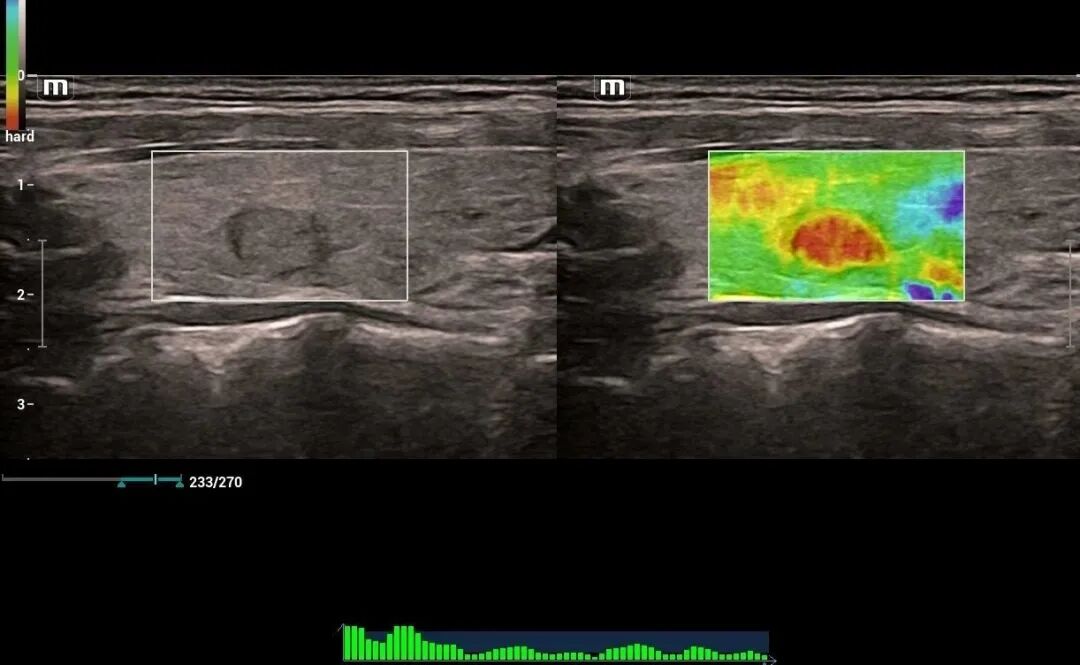

为进一步提高我院诊疗检查与诊断水平,不断满足城乡患者日益增长的就医需求,健全和完善医疗保障体系。2022年12月我院引进了mindray- Resonal9T高端彩色多普勒超声系统正式投入使用,此设备具备超声介入、超声造影、超声高帧率 STE 剪切波弹性成像及应变式弹性成像(甲状腺、乳腺、肝脏),二维、三维、四维、阴式、盆底、心脏及血管超声等功能。此设备的引进标志着海伦影像学科将跨越新的高度,以此助力城乡百姓解决看病难,看病贵的就医难题!

3.体表器官。如乳腺肿物、乳腺增生、甲状腺肿瘤、甲状腺炎。